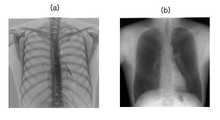

도 9의 (a)는 본 발명의 일 실시예에 따른 이중 에너지 엑스선 영상 장치의 제어방법에 의해 획득된 고에너지의 흉부 엑스선 영상이다.

도 9의 (b)는 본 발명의 일 실시예에 따른 이중 에너지 엑스선 영상 장치의 제어방법에 의해 획득된 저에너지의 흉부 엑스선 영상이다.

호스트 컴퓨터(40)는 전송된 전기 신호로부터 저에너지의 엑스선 영상을 획득한다. 도 9에 고에너지와 저에너지의 흉부 엑스선 영상이 도시되어 있다. 도 9a가 고에너지의 흉부 엑스선 영상이고 도 9b가 저에너지의 흉부 엑스선 영상이다.The

그리고 호스트 컴퓨터(40)는 고에너지를 갖는 엑스선의 뼈와 연조직에 대한 감쇠계수, 저에너지를 갖는 엑스선의 뼈와 연조직에 대한 감쇠계수에 기초하여 뼈 또는 연조직에 대한 이중 에너지 엑스선 영상을 획득한다. 도 10에 엑스선의 에너지에 따른 뼈와 연조직의 감쇠계수 그래프가 도시되어 있다.The